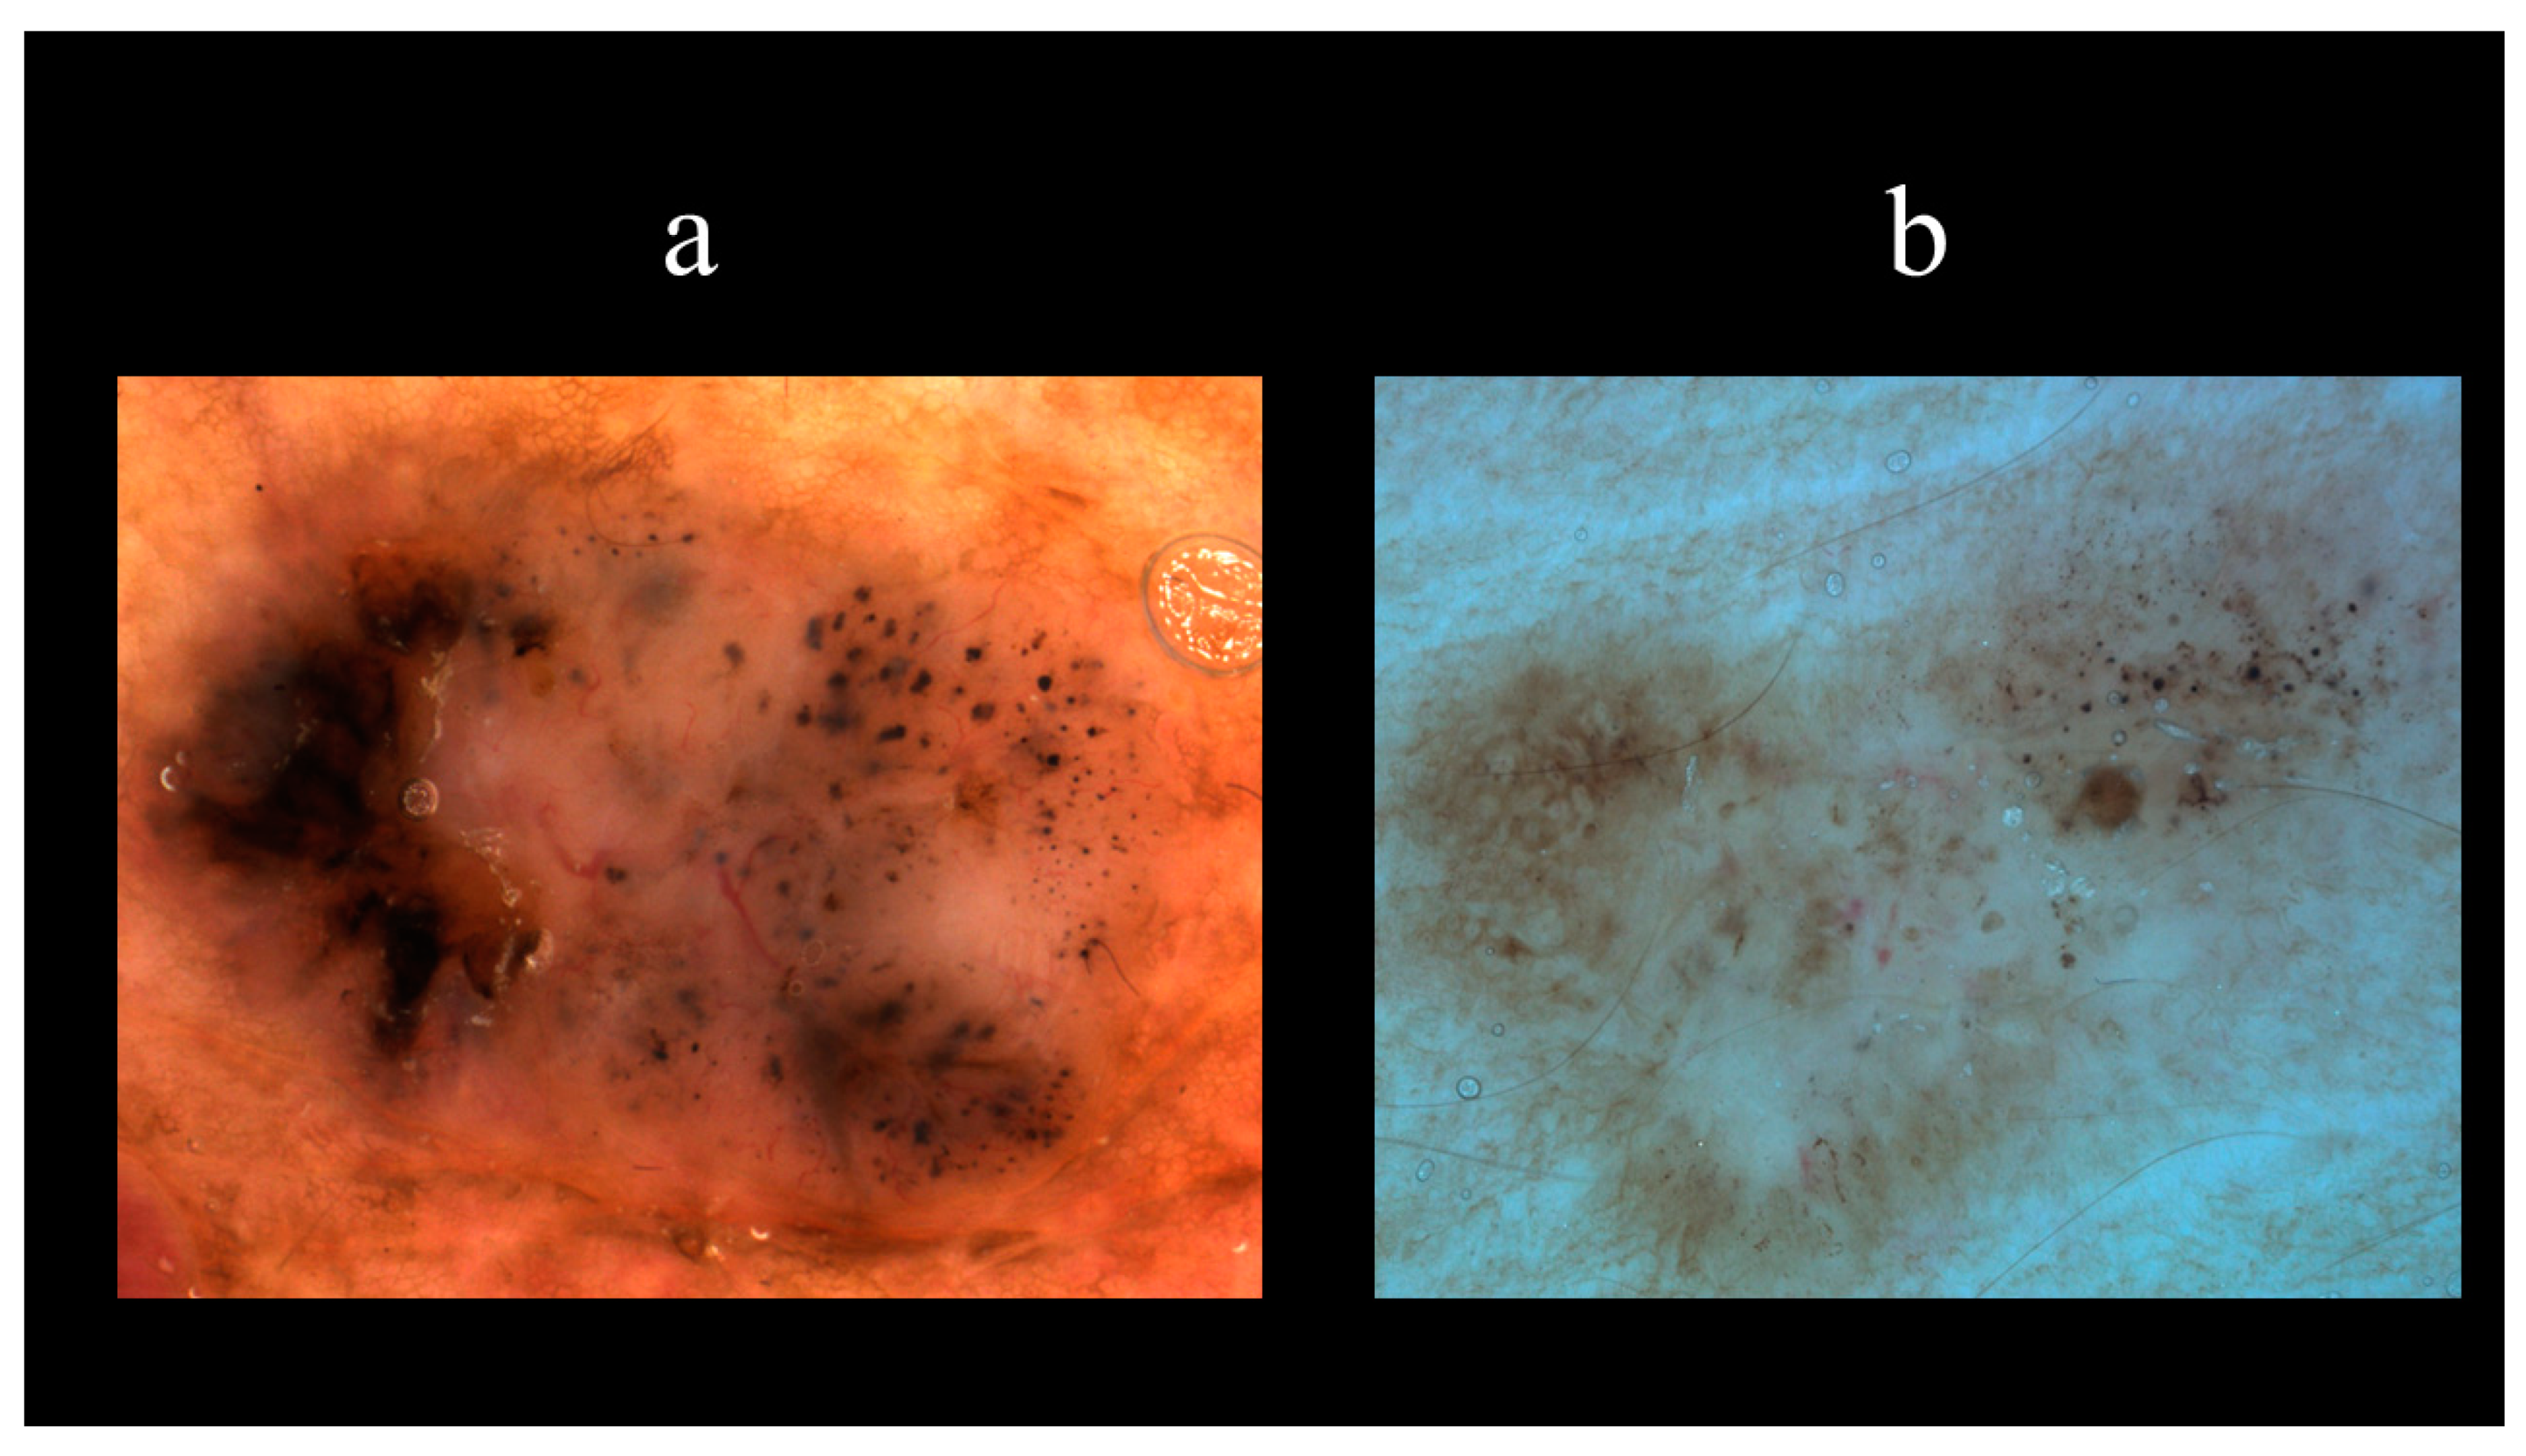

5. Dermoscopy